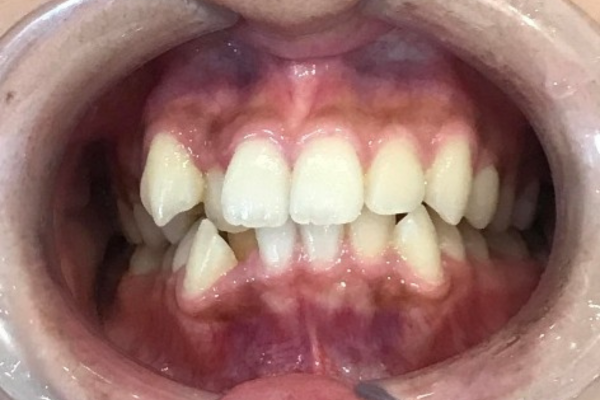

叢生|マウスピース矯正(インビザライン)の症例

インビザライン

上下の前歯のガタツキ

1年半

装着中の違和感

虫歯、歯肉炎